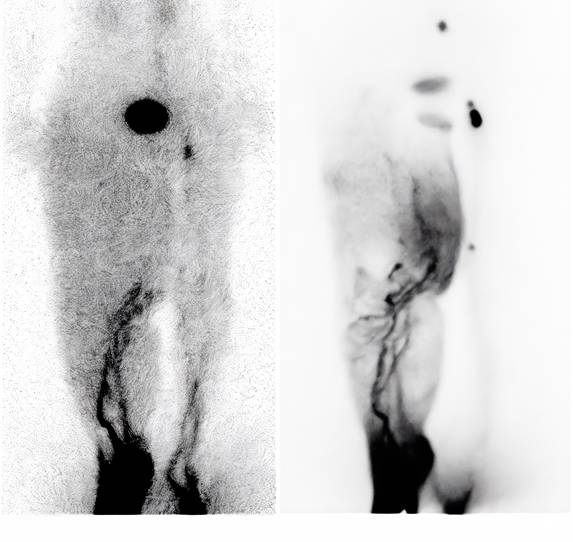

Lymphoscintigraphy findings

Seven patients underwent lymphoscintigraphy at 12 months. All demonstrated findings suggestive of functional improvement, including increased tracer uptake in the transferred omental flap (Figure 5), clearer visualisation of lymphatic trunks, reduced dermal backflow, and fewer collateral channels (Figure 6). Comparative analysis was not feasible in five patients due to flap failure (n = 1), loss to follow-up (n = 1), or incompatible preoperative imaging protocols (n = 3).

Figure 6

(A) Preoperative lymphoscintigraphy showing dermal backflow throughout the right leg, with main lymphatic vessels visible only below knee level. (B) Lymphoscintigraphy one year postoperatively showing significant improvement in lymphatic drainage. Main lymphatic vessels were visible above knee level, with reduced dermal backflow.

These findings are consistent with previous reports by Ciudad et al.[12] and Nguyen et al. [18, 22], who demonstrated clinical and functional improvement following laparoscopic omental VLNT. Our results are further corroborated by recent extensive clinical experiences reported by Pozzi et al., which reaffirmed that gastroepiploic VLNT is a highly effective and safe procedure for extremity lymphedema, offering significant improvements in limb circumference and tissue tonicity with minimal donor-site morbidity [26]. Notably, our lymphoscintigraphy suggested not only improved drainage but also radiotracer uptake within the transferred flap, supporting the concept of neo-lymph node formation through lymphangiogenesis and functional integration into the host lymphatic network. This aligns with prior experimental studies showing that transplanted lymph nodes secrete VEGF-C and VEGF-D, which stimulate VEGFR-3-mediated lymphangiogenesis and promote the regeneration of lymphatic sinuses and high endothelial venules (HEVs) [12, 18, 22].

The observed greater reduction in distal limb circumference further supports the biological mechanism: placing the omental flap at the ankle optimises gravitational drainage and provides a local microenvironment for lymphangiogenesis. The improved uptake and reduced dermal backflow on lymphoscintigraphy are consistent with the establishment of new lymphatic pathways and the functional maturation of neo-lymph nodes.